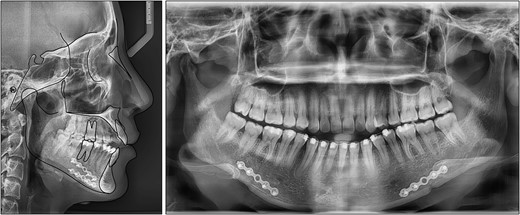

After 8 months of distalization, class I canine and molar relationships were obtained. To address the overbite by posterior intrusion of maxillary molars, two additional mini-screws were implanted into the buccal alveolar bone between the maxillary first and second molars (Fig. 4). The total treatment time was 19 months.

After treatment, class I canine and molar relationships were obtained on both sides with a normal overjet and positive overbite (Fig. 5). The posttreatment lateral cephalometric evaluation showed an improvement in both anteroposterior (point A-nasion-point B angle, 3.1°) and vertical dimensions (Frankfort mandibular angle, 31.0°). The posttreatment panoramic radiograph showed adequate root parallelism without any sign of root resorption (Fig. 6). The lateral cephalometric superimpositions confirmed the intrusion of the maxillary molars, the extrusions of the incisors, and the counter-clockwise autorotation of the mandible (Fig. 7).